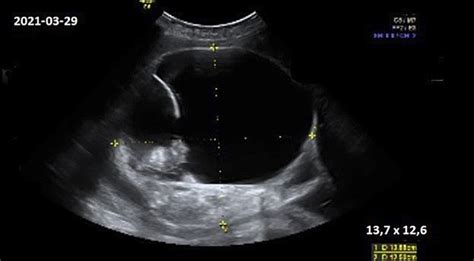

Spermatozoidui apvaisinus kiaušialąstę ir nėštumui užsimezgus, moters organizmas pradeda gaminti nėštumo hormonus, formuojasi gemalinis maišelis (kitaip dar vadinamas trynio maišeliu) ir placenta. Gemalinis maišelis yra pirmasis matomas nėštumo požymis ultragarsiniame tyrime. Iki 5 nėštumo savaitės gimdoje jau turi būti matoma gemalinė pūslytė. 6-7 nėštumo savaitę jau gemalinėje pūslytėje turi būti matomi ir embriono kontūrai. Be to, šiame sezamo sėklos dydžio „grūdelyje” (~2mm), t.y. embrione, turi būti matoma plakanti širdelė. Tai leidžia įsitikinti, jog gemalinė pūslytė yra gimdoje ir joje užsimezgęs embrionas, galime matyti pulsuojančią širdelę, nes pasitaiko atvejų, kai pūslytė, deja, būna tuščia.

Echoskopija, dar žinoma kaip ultragarsinis tyrimas, yra vienas dažniausiai nėštumo metu atliekamų tyrimų. Tai neinvazinis ir plačiai naudojamas metodas nėščiųjų sveikatos priežiūroje, leidžiantis įvertinti vaisiaus raidą, augimą ir būklę, taip pat nustatyti galimus nukrypimus nuo įprastos nėštumo eigos. Geriausia, kai ultragarsinis tyrimas yra atliekamas iškart - 5-7 nėštumo savaitę. Tai leidžia įsitikinti, jog gemalinė pūslytė yra gimdoje ir joje užsimezgęs embrionas.